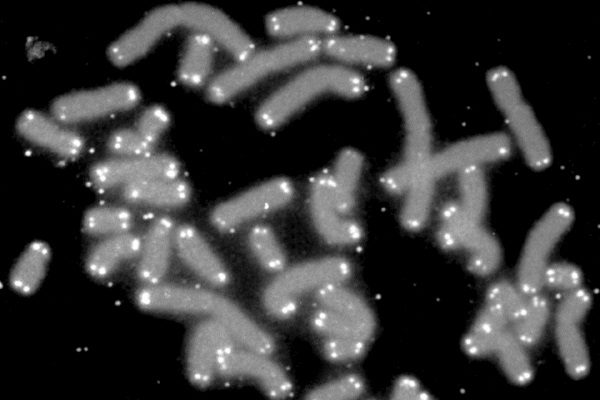

在人类细胞染色体的两端,存在着被称作端粒的DNA片段。对染色体而言,端粒就像是高跟鞋鞋跟末端的“帽子

染色体